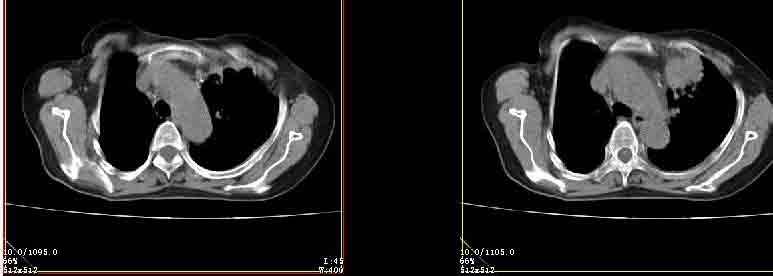

女77岁因左侧胸痛伴咳嗽入院;提示:病灶平扫45hu,强化145hu补充:双肺内未闻及干湿罗音

我的诊断意见:左肺上叶前段肺癌伴节段性不张。

在不张的肺内见到不规则的软组织,而且强化是不均匀的(该点可能是我的图像作得不好的原因)。

右肺近胸膜下区散在结节,性质?

请教左侧肺含气不良用什么解释更好?